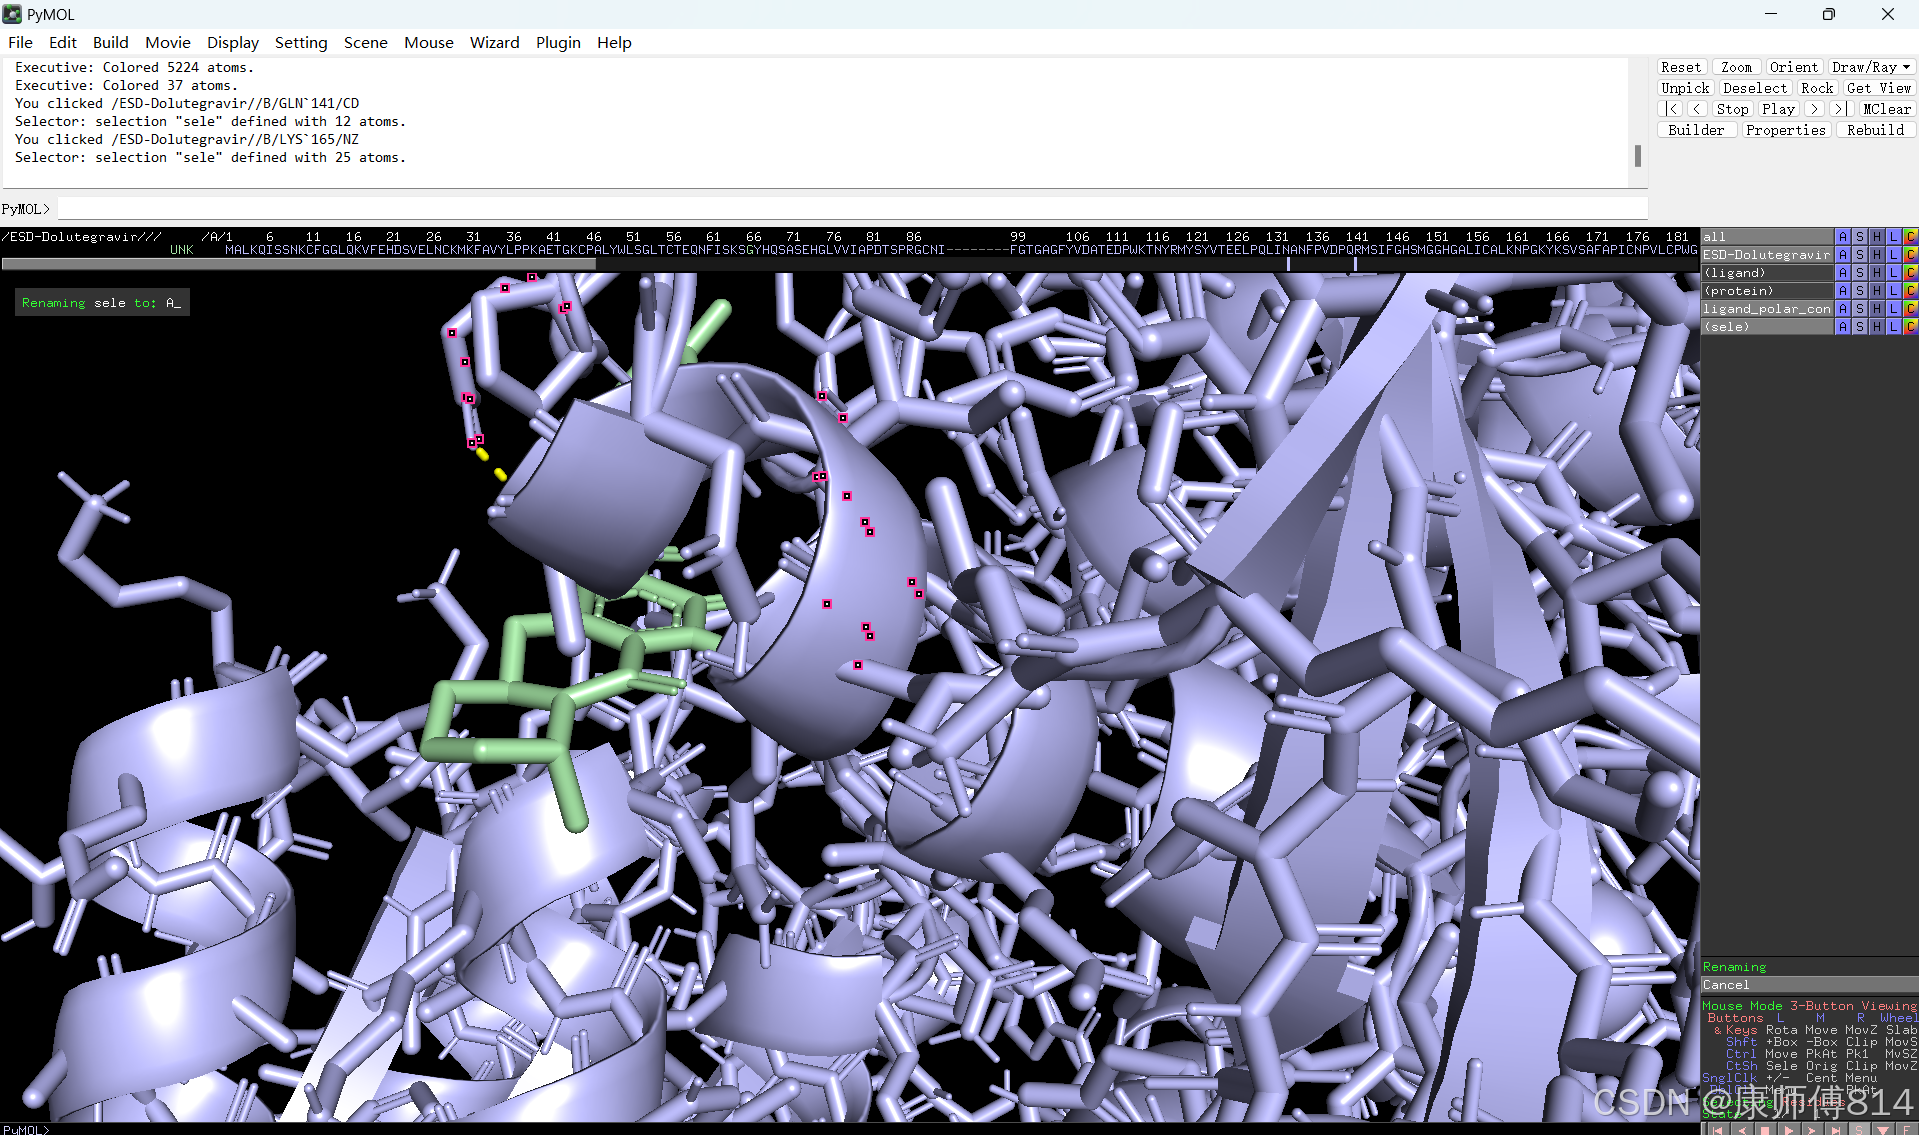

#选中蛋白,点击show-sticks显示氨基酸棍状结构,右下角Selecting修改为Residues模式,选中与小分子连接的氨基酸残基,命名为A,并更改颜色

#点击蛋白,点击H-sicks隐藏蛋白棍状结构,然后显示小分子结合位点氨基酸残基棍状结构

#此时展示分子对接的基本要素已经形成,后续可根据需要修改背景颜色、显示氨基酸残基名字以及氢键键能等等,这里不再赘述

#修改好后就可以导出了,点击右上角Draw,选择合适的格式导出即可

结果演示